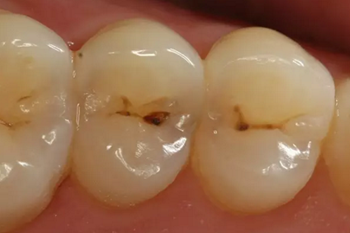

第二步:中齲

當(dāng)您吃糖時,感覺酸疼,您說:“沒關(guān)系,不是很疼。”

牙醫(yī)卻說:“這時病變已經(jīng)破壞到牙本質(zhì)淺層了,牙齒已經(jīng)有齲洞形成,對酸甜食物敏感,需要做充填治療。”